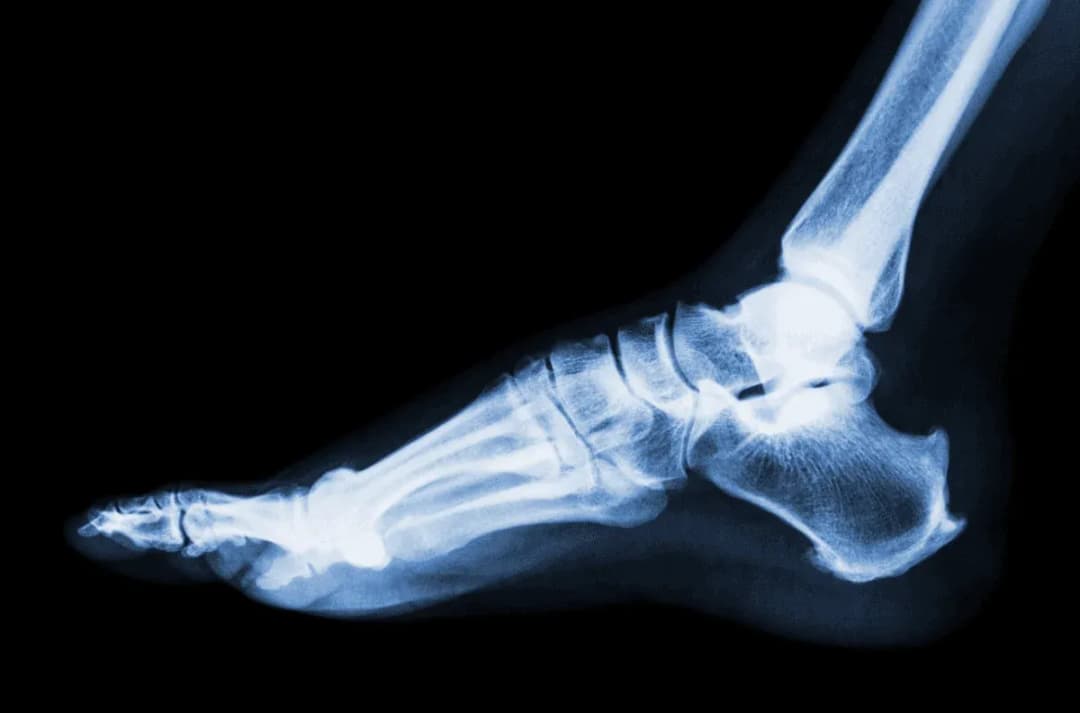

Tag objawy skręcenia stawu skokowego